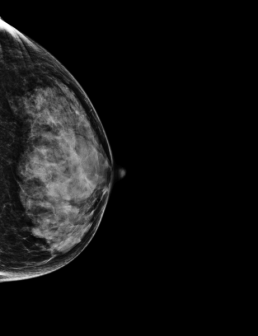

Mammographie de dépistage sur seins denses (D) en 2020.

Ici, une asymétrie lobulée de 6,5 mm de diamètre sans calcifications associées est détectée sur le sein droit, à 9 cm du mamelon.

Une autre mammographie et échographie confirment la présence de la lésion à 9.30.

La biopsie révèle la présence d’un carcinome canalaire invasif (IDC).

En examinant la mammographie initiale de 2019, avec l’utilisation rétrospective de MammoScreen, il semble que l’IA ait détecté la lésion sur les deux vues (CC et MLO). MammoScreen donne un score de 8, indiquant un soupçon élevé, et alertant sur la malignité potentielle de ce cas.